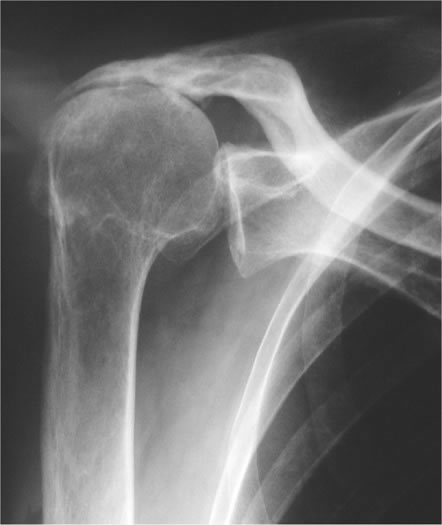

Dabei geraten knorpelaufbauende und -abbauende Prozesse aus dem Gleichgewicht und es kommt zu einem Verlust der schützenden Knorpelschicht. Schulterarthrose ist der Gelenkverschleiß des Schultergelenks. Als Schulterarthrose Omarthrose wird der chronische Gelenkverschleiß im Schultergelenk bezeichnet.

Hier kann es sinnvoll sein mit gezielten Übungen die Muskulatur rund um die betroffenen Gelenke zu trainieren. In der Folge breitet sich der Verschleiß auf den Knochen die Gelenkkapsel und die umliegenden Sehnen aus. Arthrose an der Schulter Schultergelenkarthrose medizinischer Fachbegriff Omarthrose.

Schmerzen und eingeschränkte Beweglichkeit der Schulter sind die Folgen. Eine Arthrose des Schultergelenks kann zu einem Absterben des Knochengewebes Knochennekrose.

Schulterarthrose Behandeln Klinik Pyramide